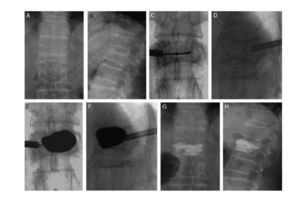

骨质疏松症已成为危害老年健康增加社会负担的一类重要疾病。椎体压缩性骨折造成的疼痛和脊柱畸形可使肺活量下降、食欲减退、减少活动量,从而导致进一步的骨量丢失,结果形成恶性循环,使生活质量下降、寿命缩短。传统采用的保守治疗效果不理想。我脊柱外科采用经皮椎体成形术( PVP) ,经皮球囊扩张椎体后凸成形术( PKP) 应用于临床并取得良好效果,目前为止,近2000例患者在我科做了PKP或PVP手术,优良率达到95%。

三、优点:球囊扩张椎体成型术术后可以迅速地缓解患者的疼痛症状,改善了压缩性骨折程度,起到了椎体内固定作用,强化了骨小梁的支撑力,对脊柱稳定性的重建更有重要作用。术后明显恢复病椎的椎体高度和改善脊柱的后凸畸形,患者可在早期(术后24小时)行腰背肌功能锻炼以及腰围保护下负重行走。大大地减少长期卧床的并发症和病死率,提高了患者的生命质量。